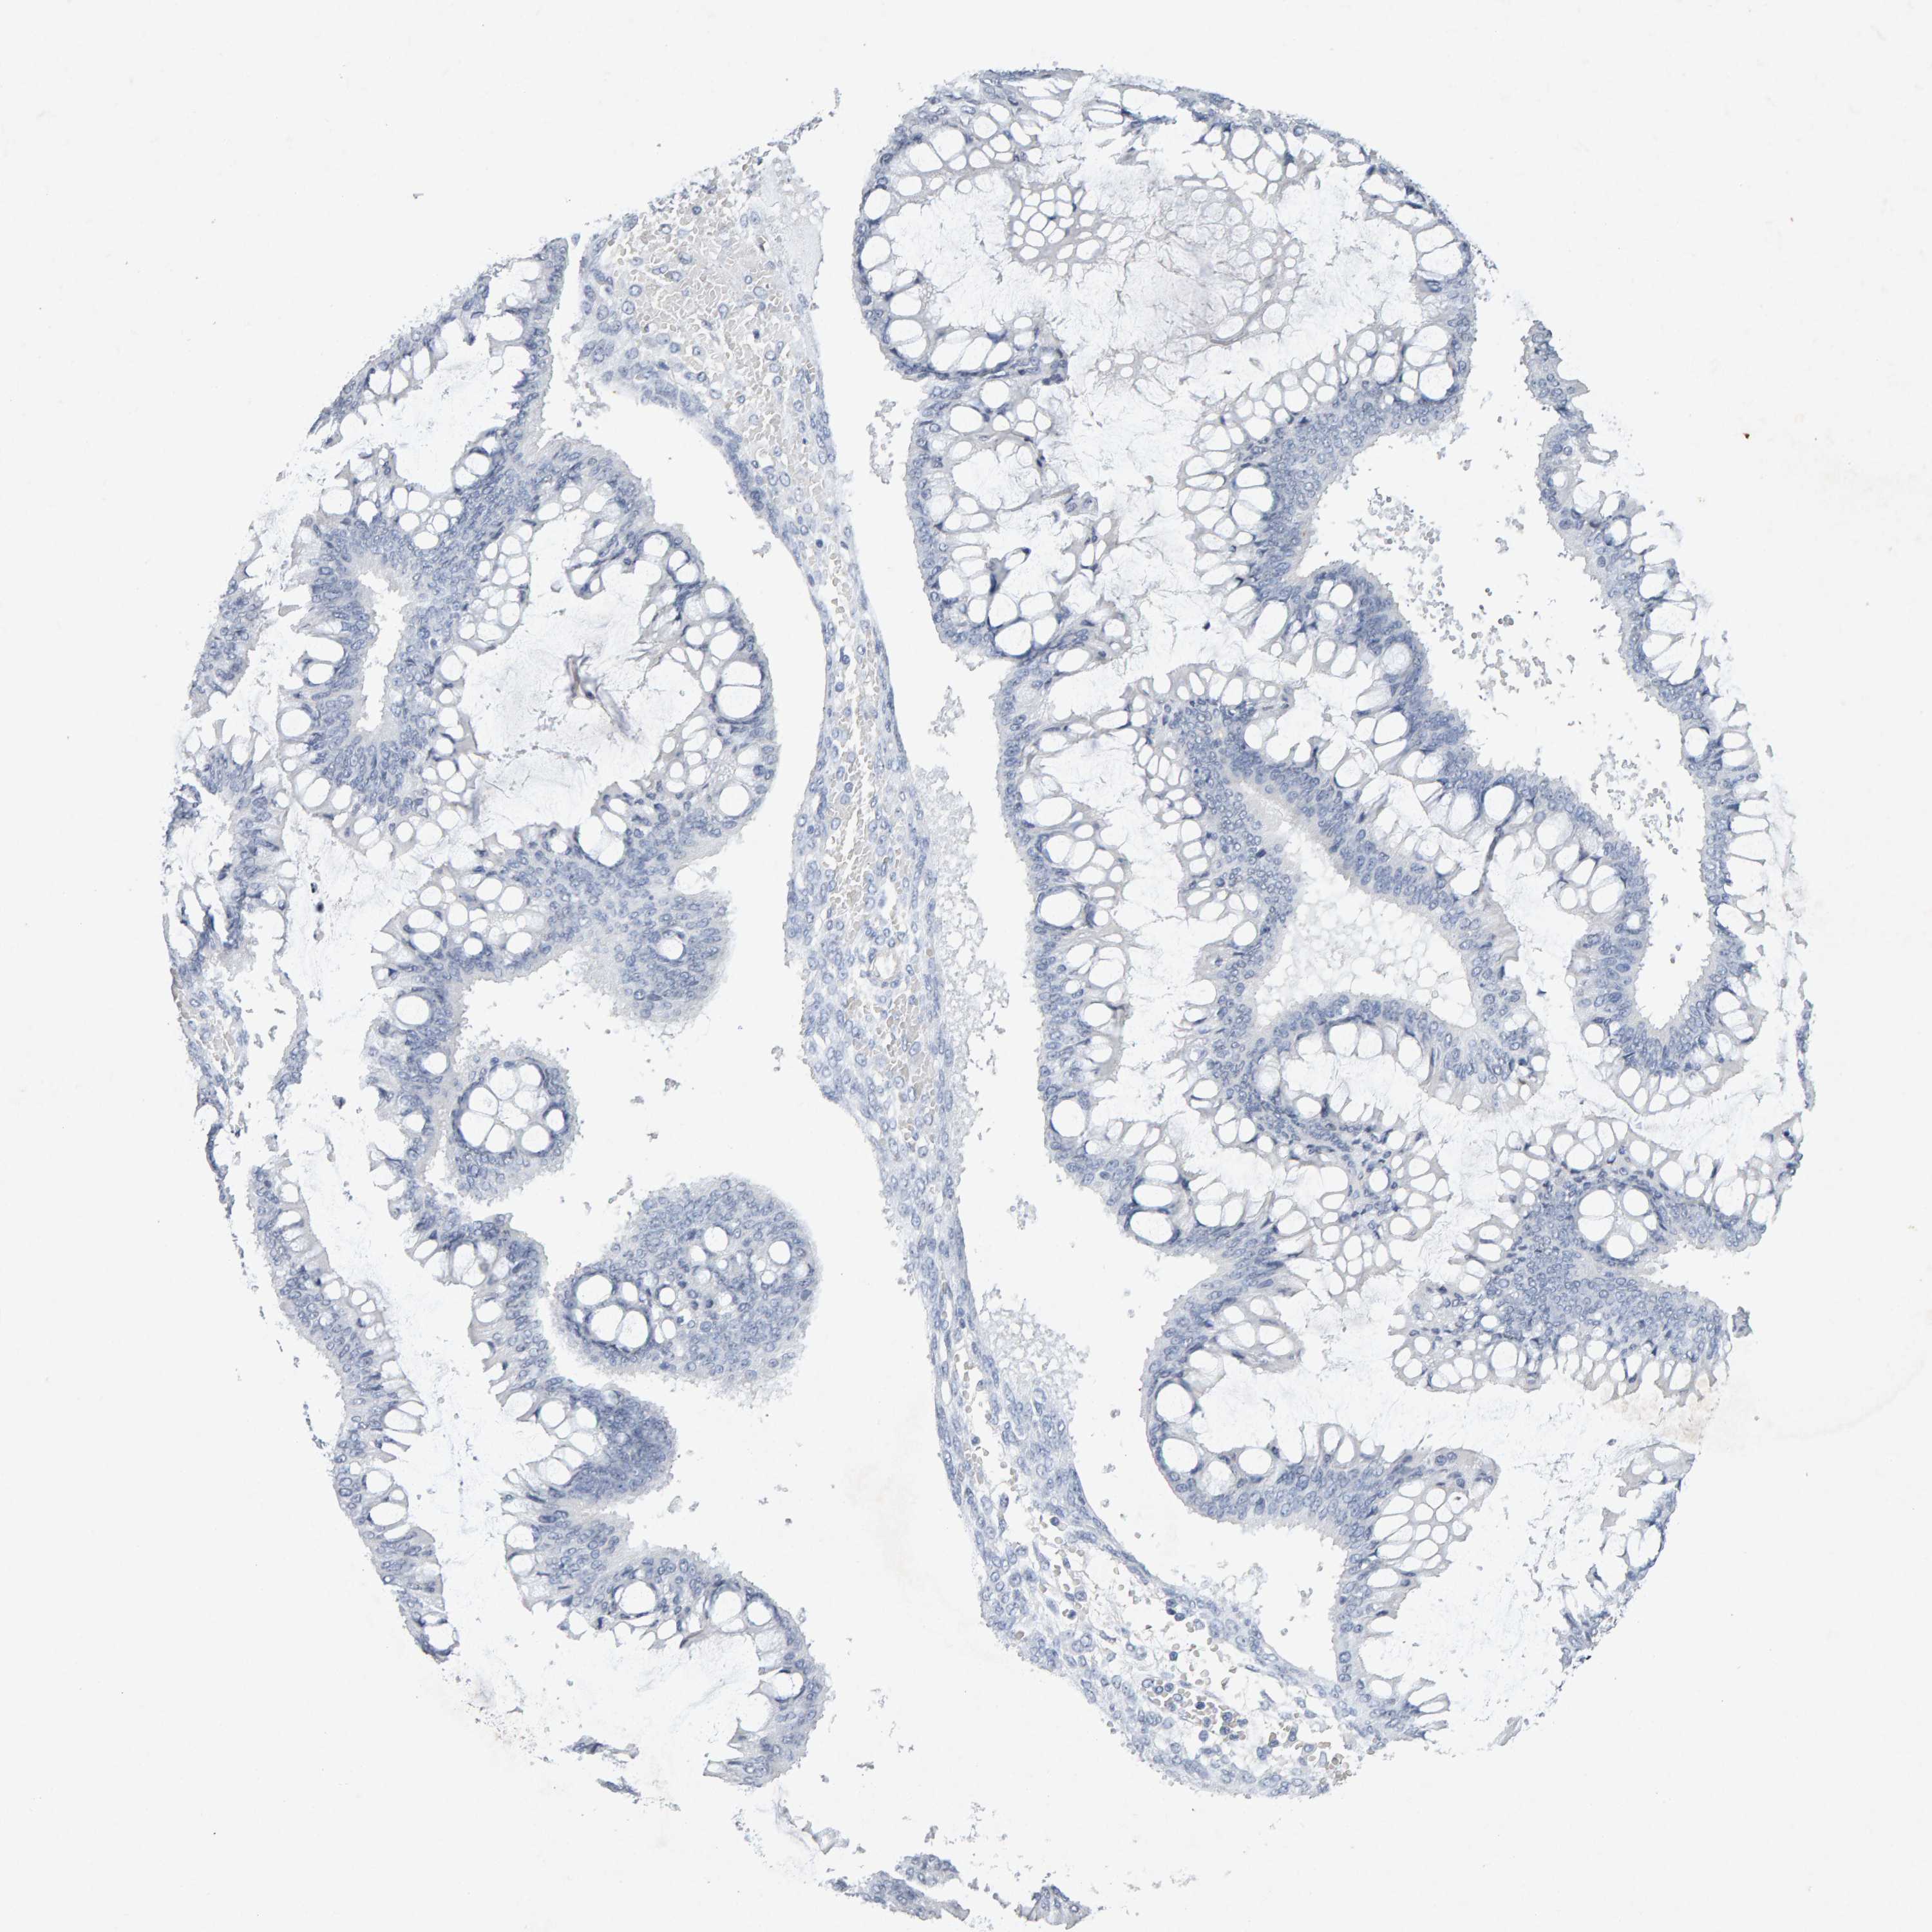

OVARIAN CANCER - Protein expressioni

A mouse-over function shows sample information and annotation data. Click on an image to view it in a full screen mode. Samples can be filtered based on level of antibody staining by selecting one or several of the following categories: high, medium, low and not detected. The assay and annotation is described here.

Note that samples used for immunohistochemistry by the Human Protein Atlas do not correspond to samples in the TCGA dataset.

Antibody stainingi

Antibody staining in the annotated cell types in the current human tissue is reported as not detected, low, medium, or high, based on conventional immunohistochemistry profiling in selected tissues. This score is based on the combination of the staining intensity and fraction of stained cells.

Each image is clickable and will lead to virtual microscopy that enables deeper exploration of all samples and also displays staining intensity scores, fraction scores and subcellular localization as well as patient and tissue information for each sample.

Antibody CAB022442

Antibody CAB022443

Carcinoma, endometroid

Cystadenocarcinoma, serous, NOS

Cystadenocarcinoma, mucinous, NOS

Carcinoma, NOS